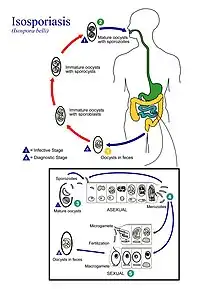

- An oocyst with one sporoblast is released in stool of infected person

- After the oocyst has been released, the sporoblast matures further and divides into two

- After the sporoblasts divide they create a cyst wall and become sporocysts

- The sporocysts each divide twice, resulting in four sporozoites

- Transmission occurs when these mature oocysts are ingested

- The sporocysts excyst in the small intestine where sporozoites are released

- The sporozoites then invade epithelial cells and schizogony is initiated

- When the schizonts rupture, merozoites are released and continue to invade more epithelial cells

- Trophozoites develop into schizonts, containing many merozoites

- After about one week, development of male and female gametocytes begin in the merozoites

- Fertilization results in the development of oocysts, which are released in the stool [1]

The sporulation time of this parasite's egg is usually 1–4 days, and the entire life cycle takes about 9–10 days.[6] The infective stage found in stool is the mature oocyst.[1] The mature oocyst for Cystoisospora belli can remain infective in the environment for months.[7]

Transmission

Cystoisospora belli does not require an intermediate host and currently is only known to transmit from person to person.[8] The method of transmission is ingesting food or water that has been contaminated with feces from someone who is infected.[1]